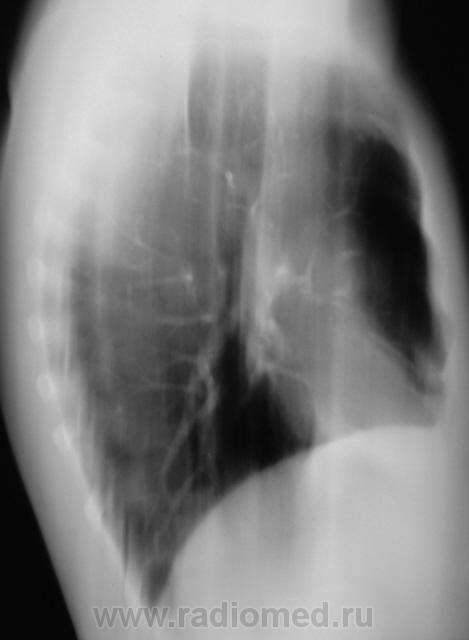

Первое исследование.